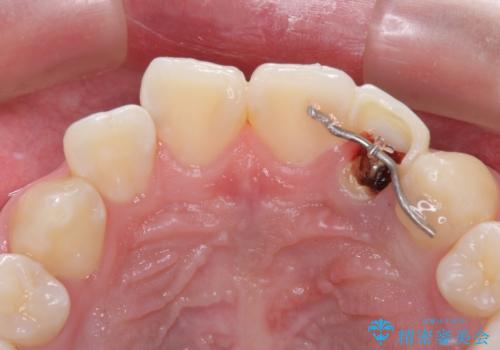

まずは部分矯正により歯を牽引し、歯肉や歯槽骨の位置を調整するために歯周外科処置を行い、治癒を待ってオールセラミッククラウンにて補綴治療を行うこととしました。